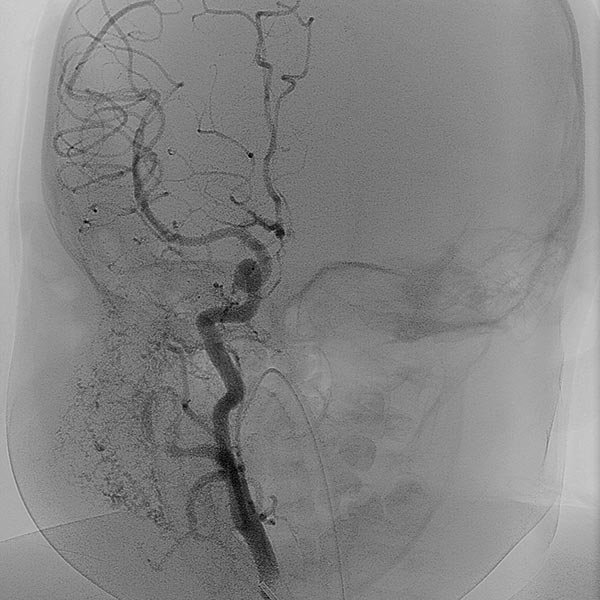

In the transarterial control angiography via the 4F diagnostic catheter, the infantile hemangioma is not perfused anymore. The typical DSA image of a “defoliated tree” is now shown.

Overview angiography via the common carotid artery after removal of the venous blocking balloon displays a virtually completely devascularized infantile hemangioma. The intracerebral circulation is normal.

Only 6 days after embolization, the subcutaneously located infantile hemangioma has decreased substantially in volume (AP view). The overlying skin did not discolor. The patient was asymptomatic from this point on, and the infantile hemangioma completely regressed within 3 months without further therapy.

After embolization, no relevant discoloration or swelling is visible even in the lateral view.